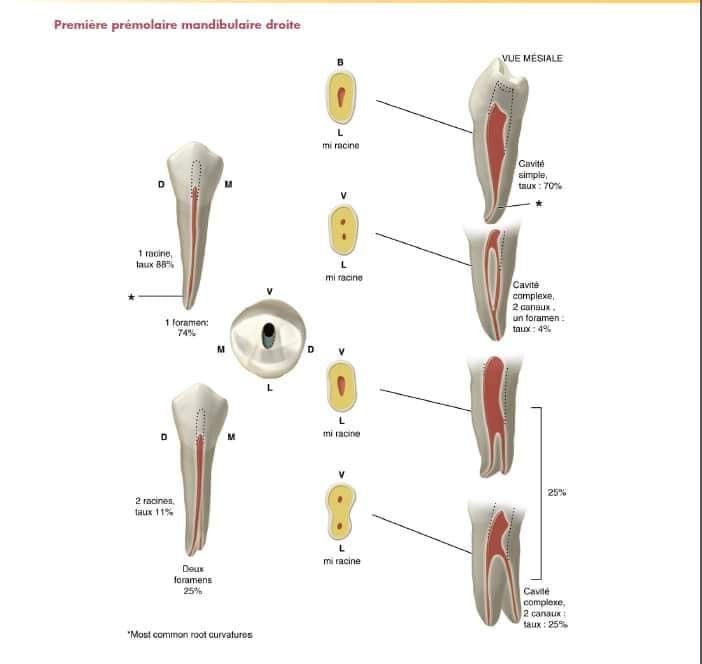

Prémolaires Mandibulaires

Première Prémolaire

Forme : ovalaire centrée sur la face occlusale

Particularité : l’asymétrie de la table occlusale déplace la forme en direction vestibulaire

Technique : approfondissement perpendiculaire standard